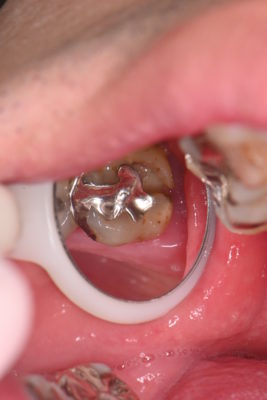

こちらの患者様は30代男性の方で奥歯が欠けてしまったと来院されました。

銀歯の下が虫歯でもろくなって欠けてしまったようです・・・

痛みなどの症状がなかったので、神経を極力残せる治療をご提案させていただきました。